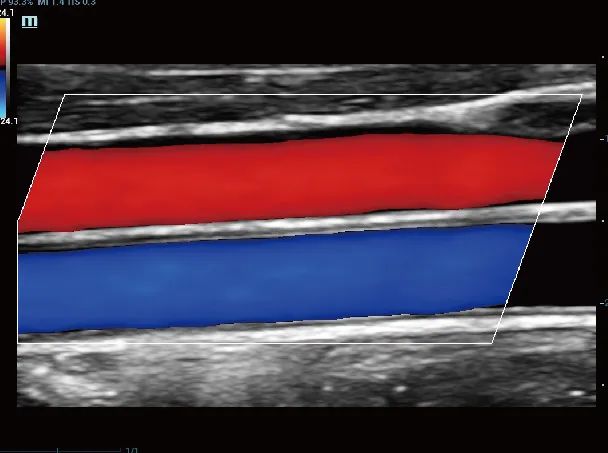

颈总动脉和颈静脉